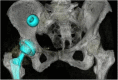

The migration of a prosthetic head during total hip arthroplasty (THA) is a rare complication. Few cases are described in the literature, offering different solutions and surgical approaches for prosthetic head retrievement. Here, we present a case of successful laparoscopic transperitoneal retrieval of a prosthetic head migrated above the right iliac vein after THA with a posterolateral approach.